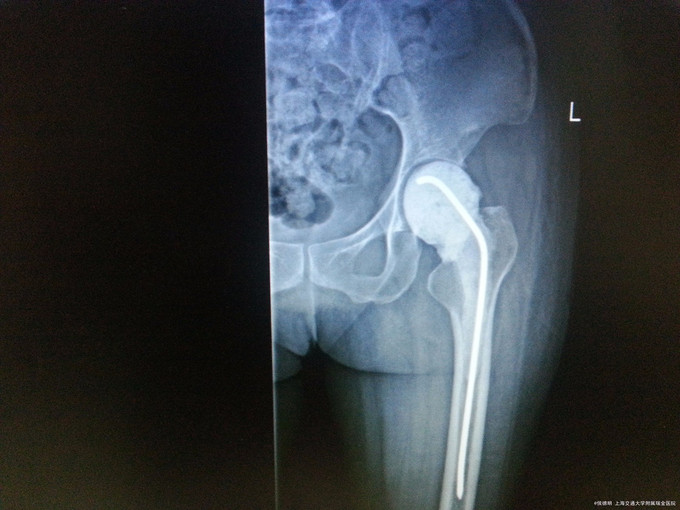

查体:左侧髋关节周围组织未见明显肿胀及发红,左髋伤口疤痕愈合好,局部皮温不高。左髋关节活动受限.左侧髋纵向叩击痛(+),右下肢无外旋、无明显缩短畸形,两下肢皮肤感觉无异常,病理征未引出。 辅检: 1.左髋MRI:左髋关节置换术后改变;股骨上段、髋臼及髂骨及周围软组织异常信号;双侧腹股沟内多发淋巴结显。 2.骨盆正位片:左侧髋关节置换术后改变,关节在位。周围软组织略肿胀。

诊断:髋关节假体置入感染(左侧) 治疗:全髋关节感染翻修(髋关节假体取出+感染清创引流+spacer植入)